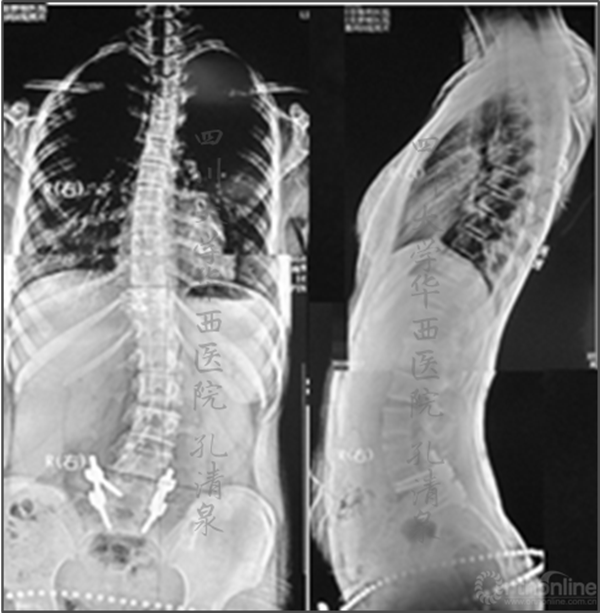

图10 术后两年半复查提示腰段侧凸加重,整个冠状面平衡尚可